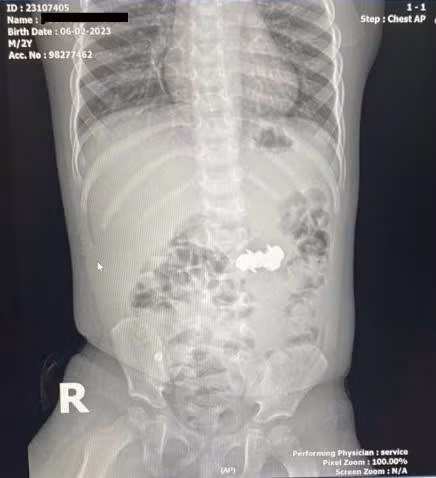

Bé D.H.P. (2 tuổi, trú tại Nghệ An) được gia đình đưa đến viện trong tình trạng nghi ngờ nuốt dị vật trong lúc chơi đồ chơi. Kết quả chụp X-quang bụng cho thấy trong ổ bụng có bốn dị vật kim loại nhỏ hình tròn, có đầu nhọn, nghi là đinh nam châm. Các viên nam châm này đã hút dính nhau trong đường tiêu hoá, tạo nên nguy cơ đặc biệt nghiêm trọng.